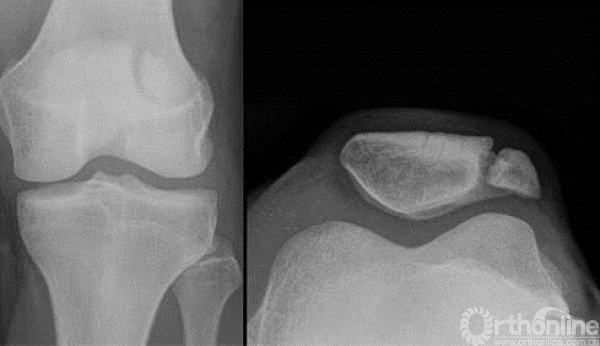

2.这例患者是否骨折?——该例病例为二分髌骨,并非髌骨骨折,发生率为8%,多数位于上外侧。

3.髌骨的血供在哪里?——主要来源于髌骨下级。